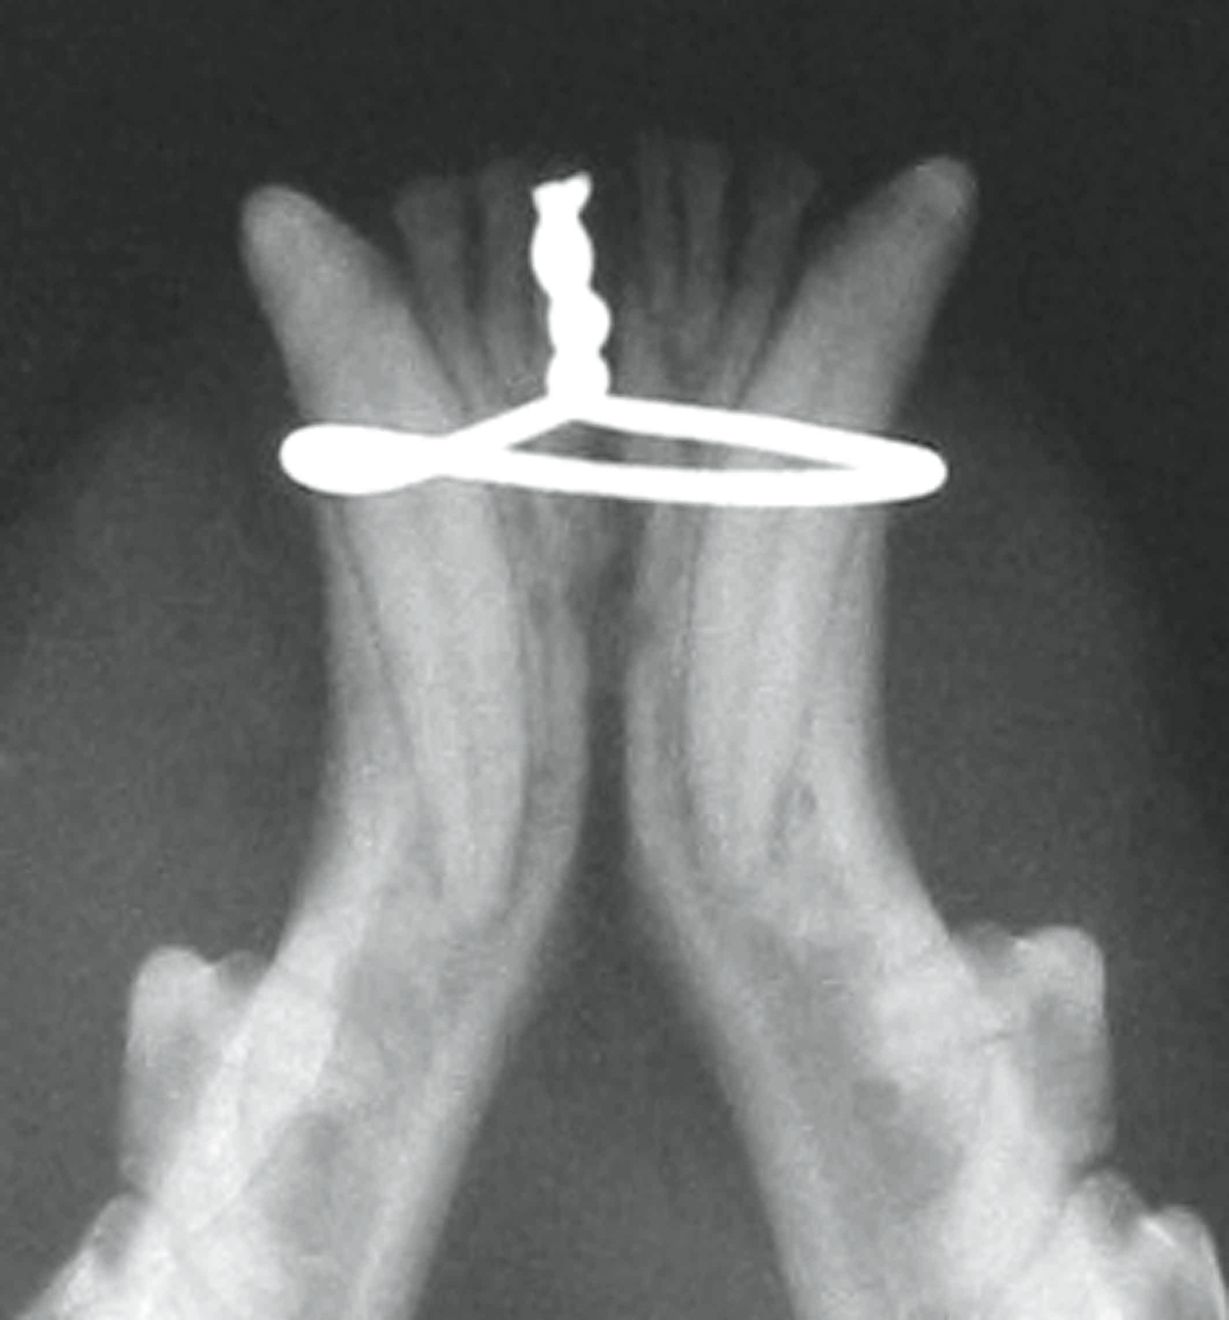

Figure 2. Disjonction de la symphyse mandibulaire traitée

Figure 2. Disjonction de la symphyse mandibulaire traitée par cerclage.© Markus Eickhoff / Thieme

Il faut veiller à ce que le placement du cerclage ne fasse pas converger les couronnes des canines inférieures, car cela pourrait entraîner un défaut d’occlusion, voire empêcher la mâchoire de se fermer. Pour éviter cela, un bridge en composite peut être fixé entre les canines inférieures. Notons que le traitement de la fracture symphysaire par vis ou broche osseuse n’est pas recommandé car il endommagerait les racines des canines.